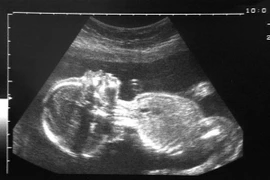

Hình ảnh về thai nhi. (Nguồn: Telegraph)

Hungary: Vẫn sinh con sau 92 ngày chết não vì đột quỵ

Các bác sỹ tại bệnh viện ở Hungary vừa lập nên kỳ tích khi duy trì thai kỳ cho một phụ nữ đã chết não 92 ngày trước khi sinh con.